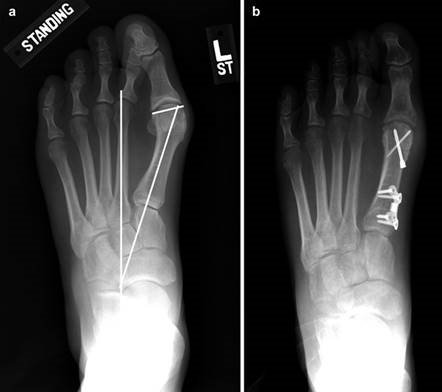

When conservative measures fail, the choice of procedure is dictated by the severity of the deformity, the presence of degenerative joint disease, and the stability of the first TMT joint. Distal osteotomies (e.g., Chevron) are generally reserved for mild to moderate deformities with an intermetatarsal angle (IMA) less than 13 degrees. Diaphyseal osteotomies (e.g., Scarf) offer greater translational correction for moderate to severe deformities. Proximal procedures, such as the Lapidus arthrodesis, are indicated for severe deformities (IMA > 15 degrees), clinical hypermobility of the first TMT joint, or recurrent hallux valgus. For hallux rigidus, joint-sparing procedures like cheilectomy are indicated for early-stage disease, while first MTP arthrodesis remains the gold standard for end-stage arthritis.

Weight-bearing anteroposterior (AP), lateral, and sesamoid axial radiographs are mandatory. On the AP view, the surgeon measures the Hallux Valgus Angle (HVA, normal < 15°), the Intermetatarsal Angle (IMA, normal < 9°), and the Distal Metatarsal Articular Angle (DMAA). The lateral view is scrutinized for Meary's angle (talo-first metatarsal angle) to identify midfoot collapse, as well as the presence of dorsal osteophytes indicative of hallux rigidus. The sesamoid axial view is critical for assessing the degree of sesamoid subluxation and the integrity of the crista.

Digital templating software is employed to determine the center of rotation of angulation (CORA) and to simulate the proposed osteotomy or fusion. This allows the surgeon to anticipate the degree of translation required, the potential for metatarsal shortening, and the appropriate size of fixation hardware. For a Lapidus procedure, templating helps calculate the exact wedge of bone to be resected from the medial cuneiform and first metatarsal base to achieve the desired multiplanar correction.